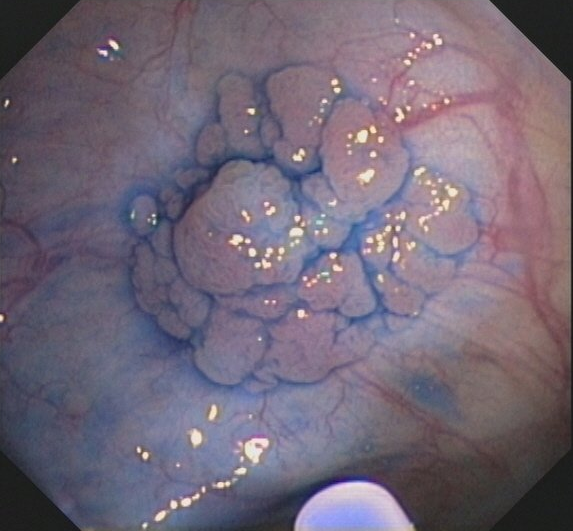

Chromoendoskopie

Manche Schleimhautveränderungen im Magen-Darm-Trakt sind bei der Endoskopie nur schwer zu erkennen bzw. abzugrenzen. Bei der Chromoendoskopie werden Farbstoffe auf die Schleimhaut aufgesprüht, dadurch werden Schleimhautveränderungen besser hervorgehoben. Proben können dann gezielt entnommen werden.

Eingesetzt werden absorptive Färbemittel, die von bestimmten Zellen aufgenommen werden, und Kontrastfärbemittel, die sich auf die Schleimhaut auflagern und das Schleimhautrelief verdeutlichen.

Zu den absorptiven Farbstoffen gehört z. B. Lugolsche Lösung, die im Ösophagus eingesetzt wird und der Früherkennung von Krebsvorstufen dient, die sich im Gegensatz zu normaler Schleimhaut nicht anfärben (Abbildung 2).